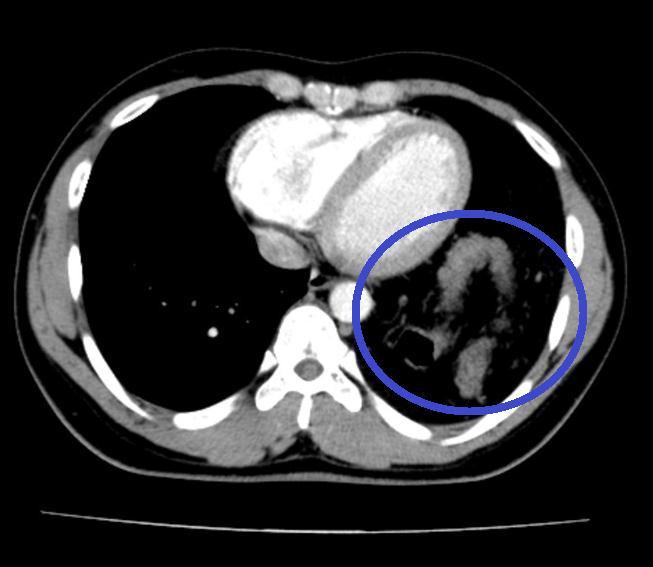

Đại tràng nằm trong ngực trái trên Cắt lớp vi tính ngực.Đại tràng nằm trong ngực trái trên Cắt lớp vi tính ngực.

Khi mổ nội soi, phẫu thuật viên nhận thấy gần toàn bộ đại tràng ngang, lách, dạ dày và mạc nối lớn đã chui qua cơ hoành lên khoang màng phổi bên trái. Sau khi đưa các tạng trên trở lại ổ bụng, tổn thương cơ hoành bên trái lộ rõ là một lỗ khuyết rộng khoảng 6x8cm.